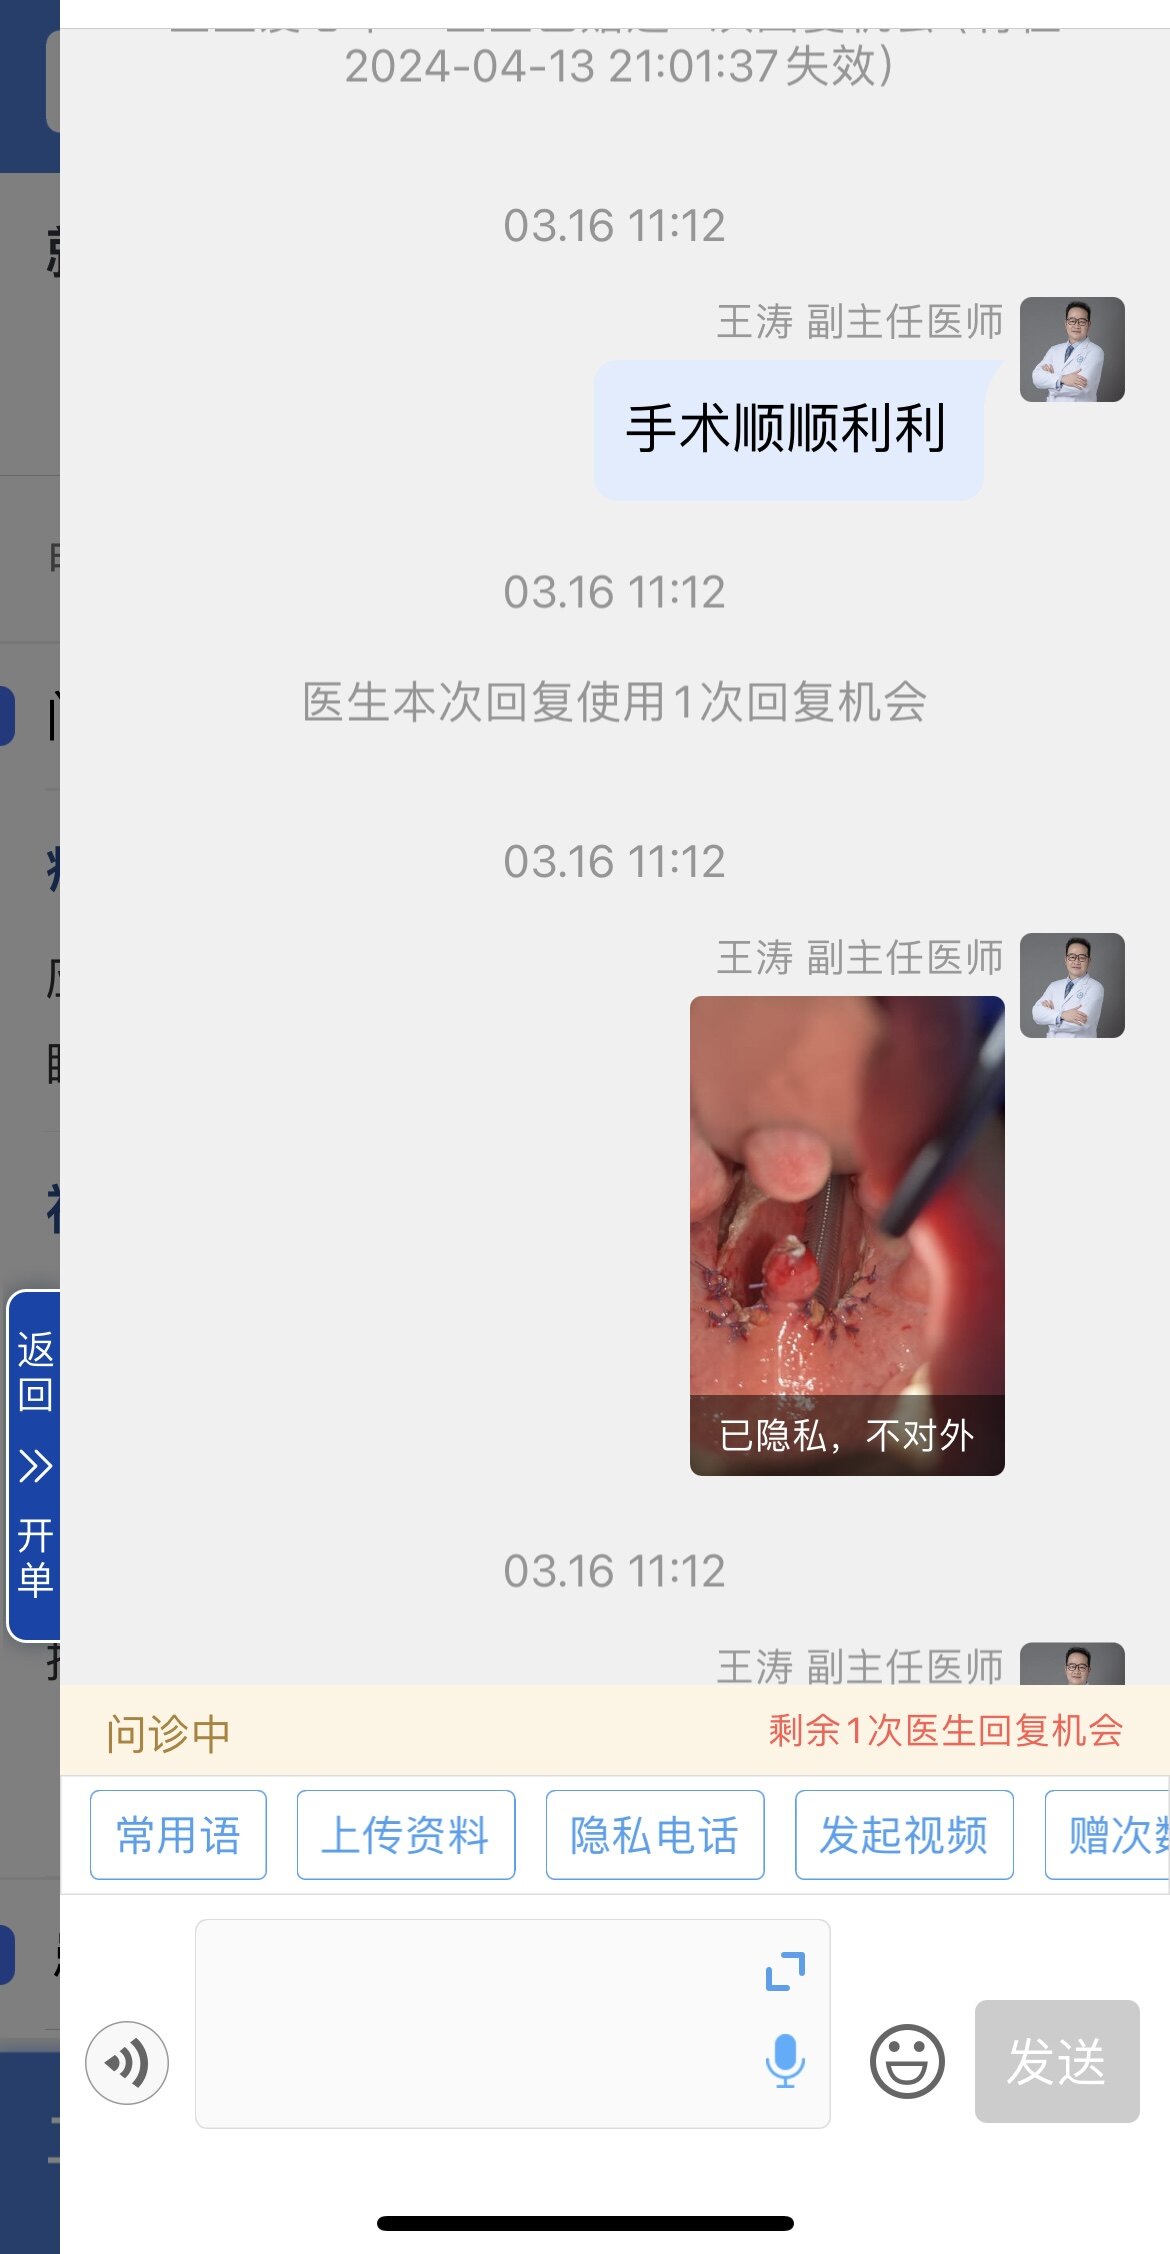

之前同一天做过“鼾症兄弟”、“鼾症兄妹”和“鼾症父女”,这是第一次给“鼾症母女”同一天手术。这对母女来自新疆巴音郭楞,重度鼾症父亲37岁,因为扁桃体肥大,自小打鼾,4年前产后打鼾加重,伴夜间憋醒,严重影响睡眠,当地医生建议患者戴呼吸机,但是她无法耐受呼吸机。电话咨询后,下定决心来广州找我手术。同时她也把4岁女儿打鼾和张口呼吸的情况也详细告诉我,鼾症女儿因为扁桃体3度肥大,腺样体堵塞后鼻孔2/3,造成张口呼吸,对于这样的孩子,一定需要早点手术干预,不然会影响面部发育和生长发育,甚至智力发育。所以我就让她们母女一起来广州找我手术。手术时发现母女俩的扁桃体肥大,因为女孩子4岁,我常规保留双下极扁桃体的1/5和腺样体的1/5。希望母女手术后身体早日恢复正常!有一个安稳的睡眠质量,健健康康的生活!

女儿的扁桃体保留双侧下极的1/5

左扁桃体下极保留1/5

肥大扁桃体

母亲手术后的咽腔

切除肥大扁桃体

处理到位的软腭层面